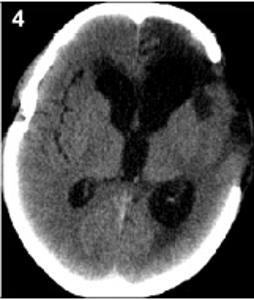

20160503094709

20160503094717

20160503094723

20160503094729